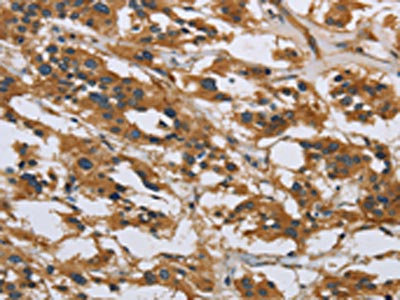

The image on the left is immunohistochemistry of paraffin-embedded Human gastric cancer tissue using CSB-PA547751(IL5RA Antibody) at dilution 1/40, on the right is treated with synthetic peptide. (Original magnification: ×200)